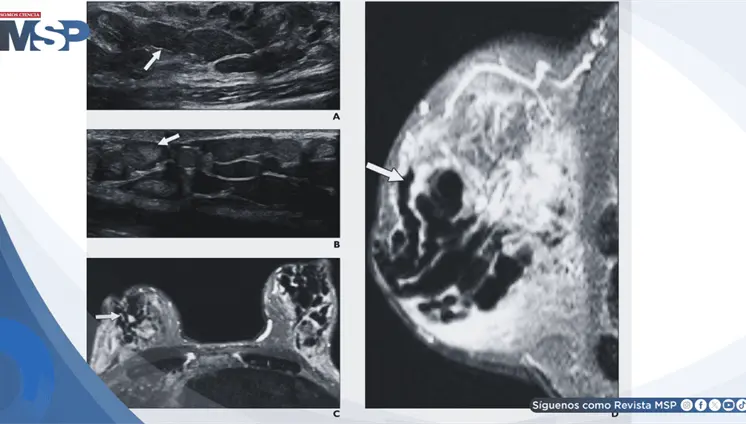

Un dolor de cabeza que empeora al estar de pie y mejora al acostarse es una señal de alerta. Esta cefalea ortostática fue la clave para identificar que no se trataba de migraña, sinusitis ni cambios hormonales, sino de un problema con la presión del líquido que rodea el cerebro.